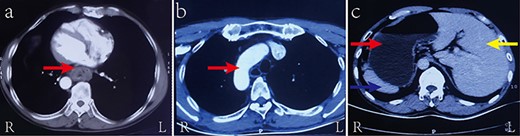

Intraoperative observation demonstrating (a) the stomach (red arrow) in the right hypochondriac region, the spleen (blue arrow) on the right rear of the stomach, and the liver (yellow arrow) on the left; (b) the azygos vein (blue arrow) and the three lobes (red arrow) in the left thoracic cavity; and (c) the esophageal carcinoma (red arrow)

the left (Fig. 3a). The patient’s stomach was routinely mobilized, the abdominal lymph node was dissected, and the anastomosis was circularly embedded with the pedicled omentum flap. An assistant abdominal incision was subsequently made below the xiphoid process, and a gastric conduit of ~3.5 cm in diameter was created using a linear stapler outside the abdominal cavity.

Before the two-port thoracoscopy-assisted thoracic surgery began, the patient was repositioned in a right prone position. The surgeon stood on the abdominal side of the patient. Intraoperative observation revealed that the azygos vein and the three lobes lay in the left thoracic cavity (Fig. 3b). A tumor 5 cm in length with a maximum diameter of 3 cm was located in the middle and lower segment of the esophagus (from 2 cm above inferior pulmonary vein to 2 cm above the diaphragm) (Fig. 3c). The esophagus was mobilized at a site 4 cm superior to the azygos vein, and the pleura surrounding the esophagus at the anastomotic stoma and thoracic lymph nodes were systematically dissected. The remaining steps in this surgery resembled that of surgery performed on situs solitus patients with esophageal cancer and consisted of purse-string suturing, the insertion of the anvil of the stapler, distal esophagectomy, and intrathoracic anastomosis of the esophageal stump and the tubular stomach.